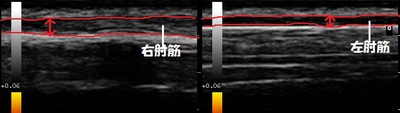

右肘 患部 左肘 正常画像

川越市 男子高校生 テニス部所属 ラケットが振れない!? 右肘関節の痛み、右肘筋炎。

来院時に右橈骨上外側部を押すと激痛が走りました。エコー(超音波)検査を行ったところ、右肘筋が

左正常部と比較して2倍ほどに腫れていました(画像の赤線)。